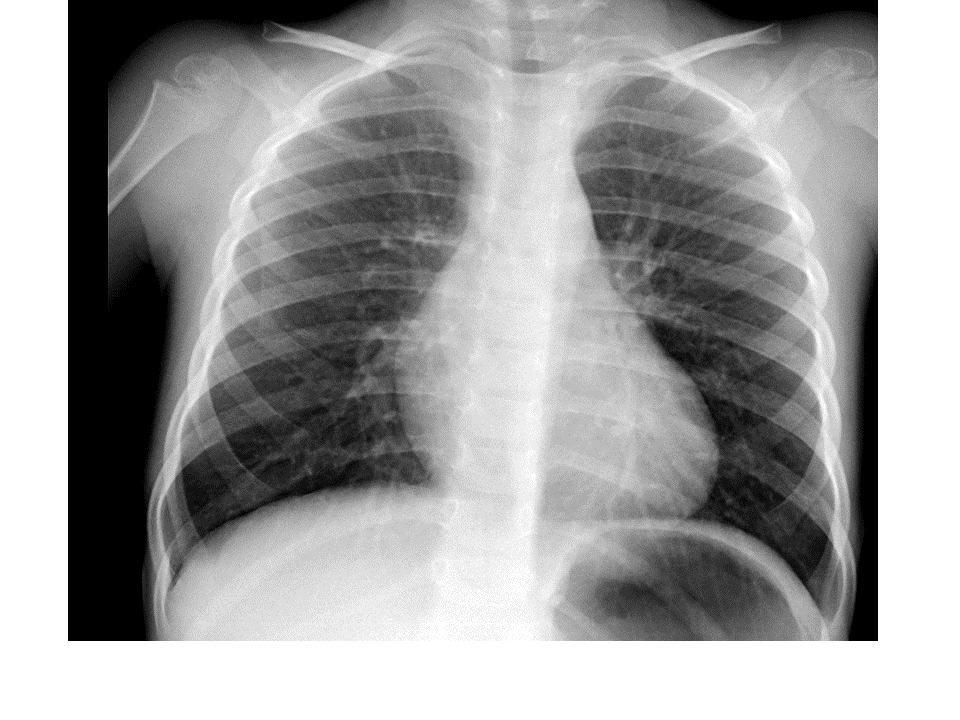

Para una adecuada lectura sistemática de la radiografía de tórax, debemos conocer la anatomía radiológica básica e identificar determinadas estructuras2.

El mediastino está formado por los contornos formados por la silueta cardiaca, la vena cava superior, el cayado aórtico y el tronco de la arteria pulmonar.